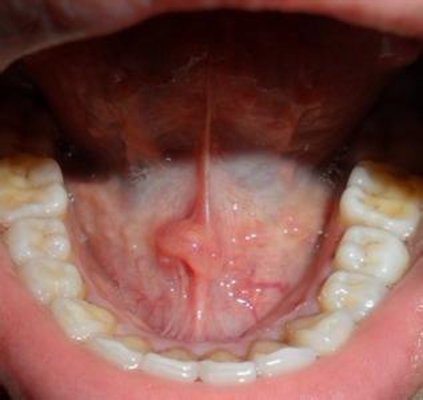

口腔癌圖片

口腔癌的前兆 (7)